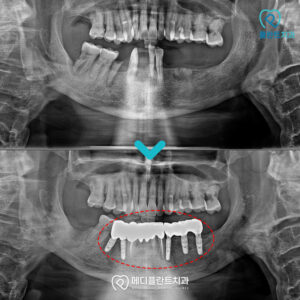

춘천수면치과 임플란트를 아프지 않게 하기 위해서는? . 안녕하세요:) 춘천수면치과 메디플란트치과입니다. . 한 번 손상된 치아는 다시 회복되기 어렵습니다. . 그렇기 때문에 평소 치아 상태를 꼼꼼히 확인하고 충치나 잇몸 문제,…